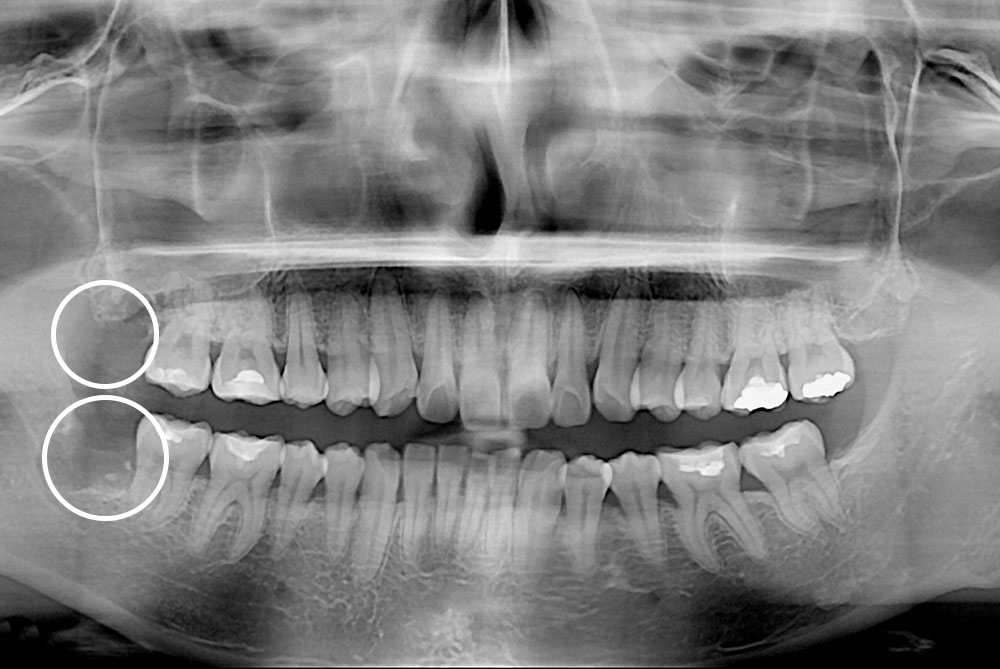

[사랑니] 매복 사랑니 발치

치료전 : 2019-02-19